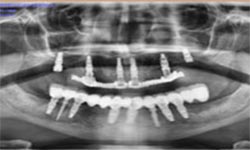

(10) Dental Implant - Full Mouth

Before Treatment

After Treatment

Patient came with a problem in chewing food and multiple loose teeth in upper and lower jaw and was interested in getting a whole new set of teeth in both the jaws. So after removal of all the weakened teeth and placement of multiple implants, he was given implant supported bridge.